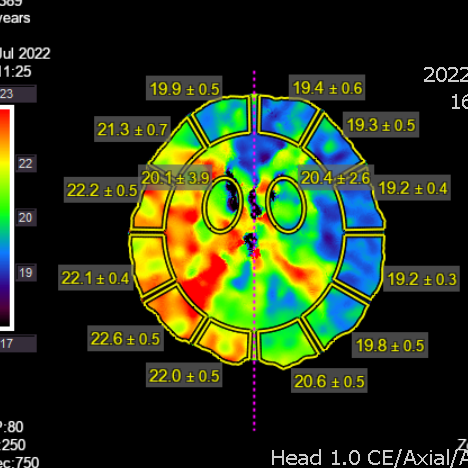

右侧相对低灌注

灌注明显改善,支持进一步随访

复查脑灌注相对缺血比术后1.5个月有加重

灌注比术前进一步改善